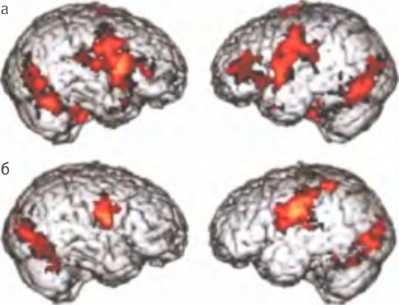

Активность мозга здорового ребенка, в том числе активность зеркальных нейронов в лобных долях (а), и пониженная активность мозга ребенка, страдающего аутизмом (б).

Результаты некоторых исследований, в которых использовались методы нейровизуализации, указывают (хотя и небесспорно) на то, что “психологическая слепота” аутистов может быть, по крайней мере отчасти, связана с нарушениями в системе зеркальных нейронов. В рамках одного такого исследования ученые сравнили активность зеркальных нейронов у детей, обладающих выдающимися способностями, но страдающих аутизмом, и у контрольной группы здоровых детей. Тех и других исследовали с помощью ФМРТ в то время, когда дети наблюдали за эмоциональными выражениями лиц и пытались их имитировать. Хотя имитация давалась детям из обеих групп одинаково хорошо, у детей-аутистов не наблюдалось никакой или почти никакой активности зеркальных нейронов в зоне коры лобных долей, играющей ключевую роль в обработке информации, связанной с эмоциями. Дети, у которых расстройство было особенно тяжелым, демонстрировали самый низкий уровень активность этих нейронов9. Другое исследование показало, что у взрослых, страдающих различными формами аутизма, кора больших полушарий в зонах, связанных с активностью зеркальных нейронов, тоньше, чем у взрослых из контрольной группы10. Это вполне логично: аутизм — это прежде всего расстройство коммуникативных способностей, то есть нарушение способности делиться чувствами, мнениями и знаниями с другими людьми.